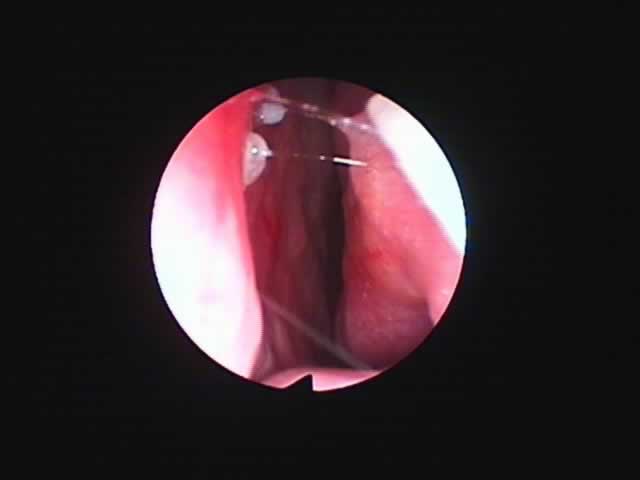

| 左扁桃術直後(31歳男性,6月9日) 数カ所針電極を刺入 | 白い部分が変性部位(6月11日) | 右扁桃術直後(7月7日) |